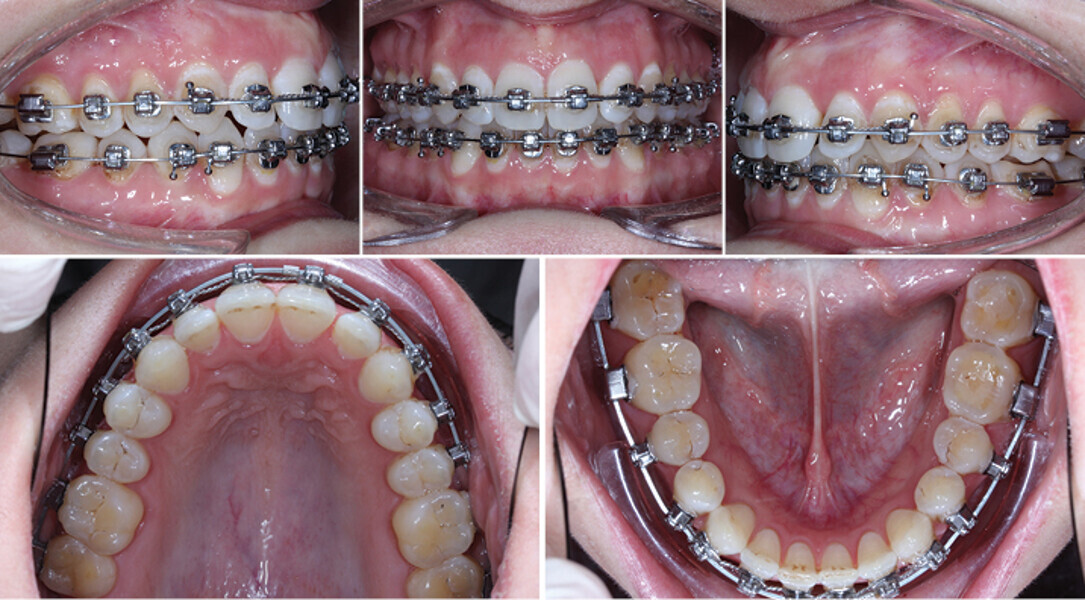

Řešení otevřeného skusu u dospělého pomocí Insignia™ systému a Straight-Wire™ finishingu